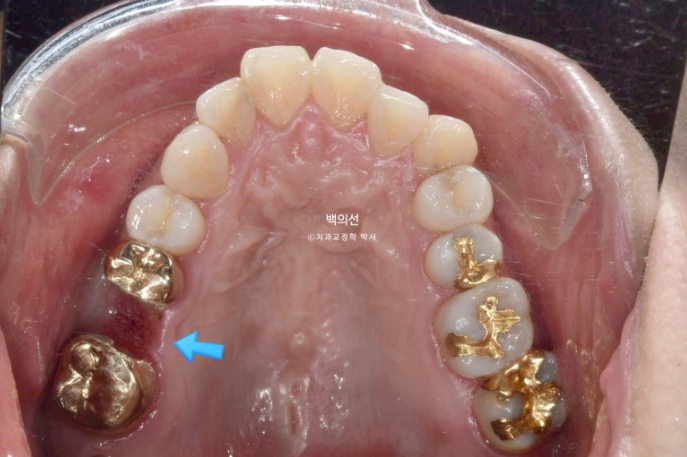

브릿지를 잘라낸 모습입니다.

클리피씨 치료를 선택하셨고 치료에 들어갔습니다.